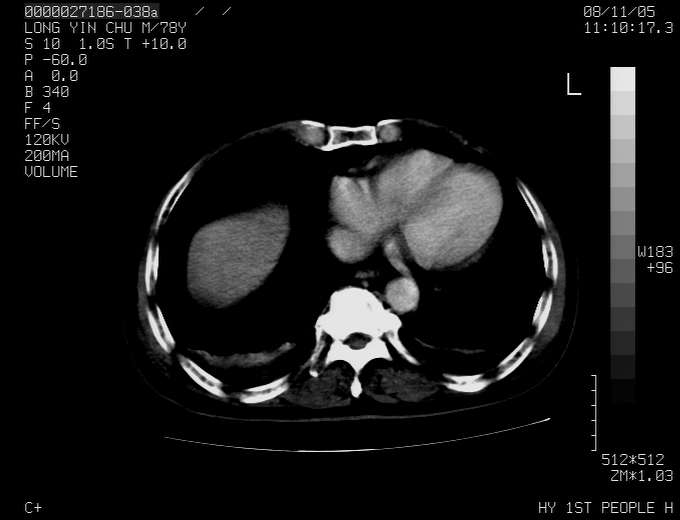

标题: CT16532:M78Y,肝脏病变,请会诊

腹胀,腹痛就诊,男性,78岁,外院b超未见异常。

肝ca,脾肾转移

支持脾肾转移瘤,双侧胸腔积液。

考虑弥漫性肝癌并脾及双肾转移.双侧胸水.

图片质量欠佳:多考虑:左侧肾癌。脾脏转移!胸膜转移!

肝脾肾转移瘤可能性大,左肾不除外梗塞,双侧胸水